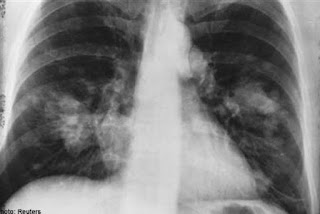

Your article about the coronavirus is correct that the crisis is being used, but your conclusion about this virus is in error: this disease is quite different from the flu or other cold viruses. This can cause permanent scarring to the lungs, even early on before the person knows they are experiencing an infection. X rays and CT scans of lungs show this (search for those terms re covid 19 and you will understand). This is not something that will just pass this season; it is released into the world and like the flu or any other virus, will return year after year, but it is bio-engineered as a bioweapon to be more lethal. So, yes, it is being used by those who oppose the USA, our Constitutional form of govt and our Bill of Rights, etc, or nations being independent of the global govt, etc. but this is a different virus and its effects are very severe in some sections of the population: especially the elderly, immuno-compromised, those with any chronic condition especially high blood pressure, COPD and other respiratory conditions, etc.